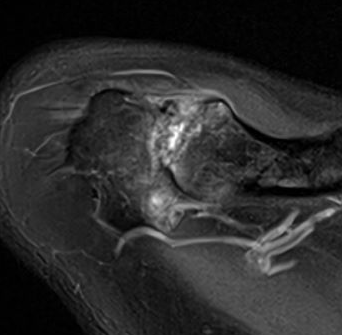

MRI

Acromioclavicular joint osteolysis